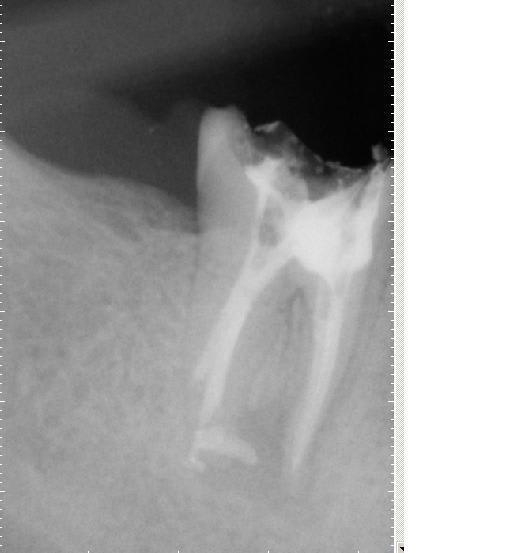

Raté puisque je finis à l'instant une reprise d'endo + kyste surinfecté sous coiffe richemont 47 scellée au verre iono (et racines sans traitement endo notable mais obturées au même verre iono, un plaisir)..... 3/4 d'heure ce matin et 1h 30 de plus ce soir mais je l'ai eue.... merci lokki et les huiles essentielles :0)

ps: le faux canal de taille de l'ancrage sur endo refaite c'est pas moi....

Richemont kkeetx - Eugenol

Reprise endo auvqay - Eugenol